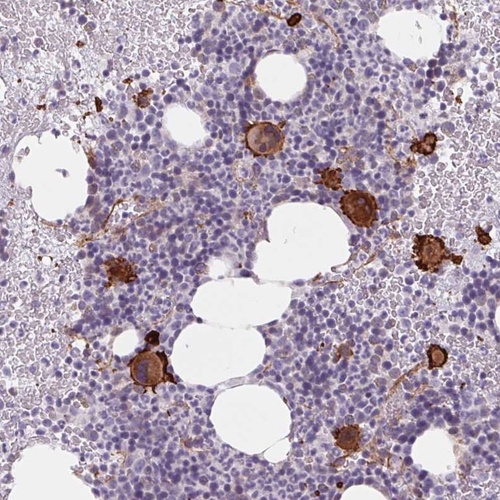

Immunohistochemical staining of human bone marrow shows strong cytoplasmic and membranous positivity in hematopoietic cells.